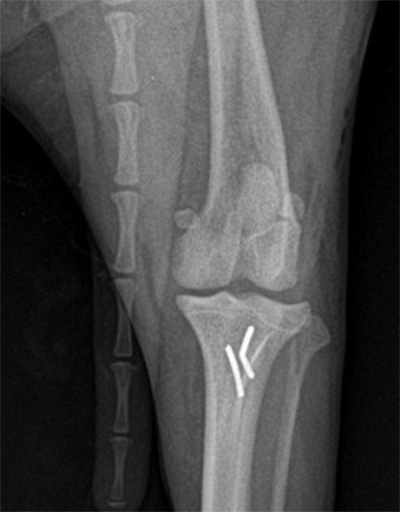

四肢の筋肉、骨、関節、脊柱疾患や外傷を扱う外科の分野です。特に獣医療では骨折や靭帯断裂、椎間板ヘルニア等の疾患が多くみられます。その原因は外傷性(けが)や先天性(生まれつき)のもの、成長期の過程で発症するもの等様々です。動物の整形外科疾患の病気は慢性経過とならないよういち早く見つけ適切な処置を行うことが必要となります。